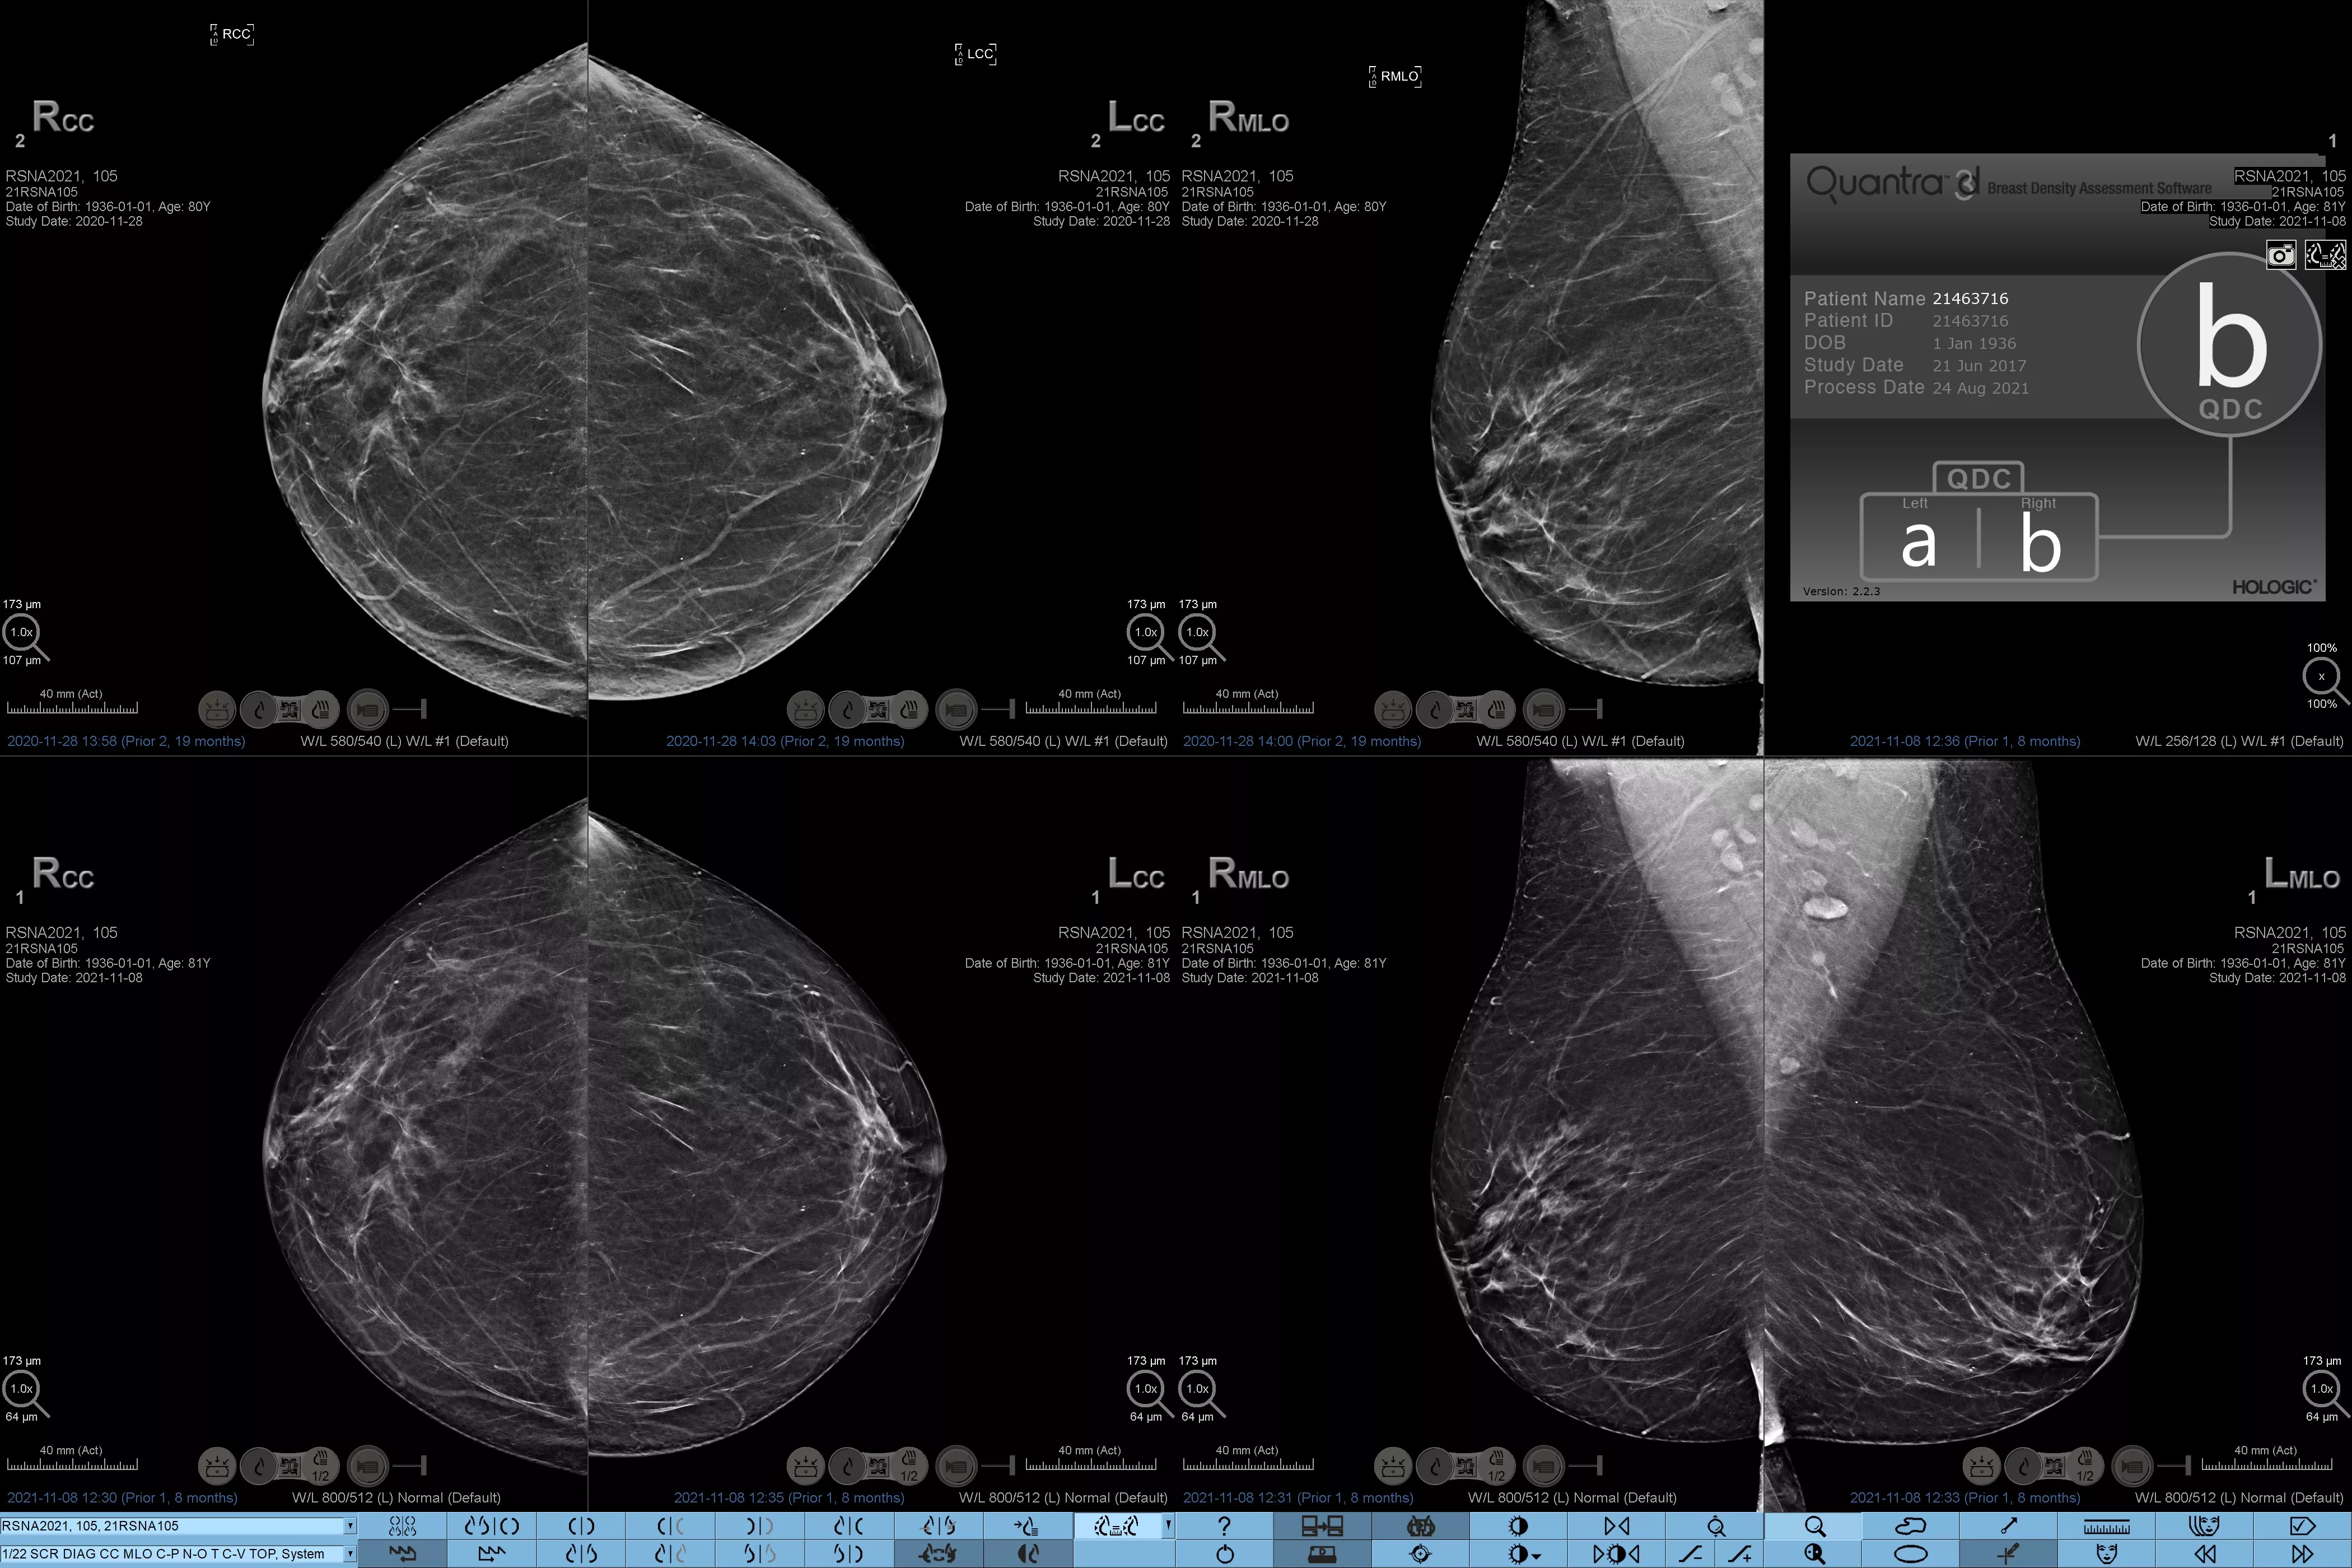

Higher breast density is known to increase a woman’s risk for breast cancer.1 The need for accurate, unbiased analysis is therefore critical. Powered by machine learning, Quantra technology software analyses both 2D™ and tomosynthesis images for distribution and texture of parenchymal tissue. It categorises breasts in four breast composition categories consistent with guidance from the American College of Radiology (ACR) BI-RADS Atlas 5th Edition.2

Objective machine learning algorithm that assigns breast density category based on analysis of breast tissue texture and patterns.